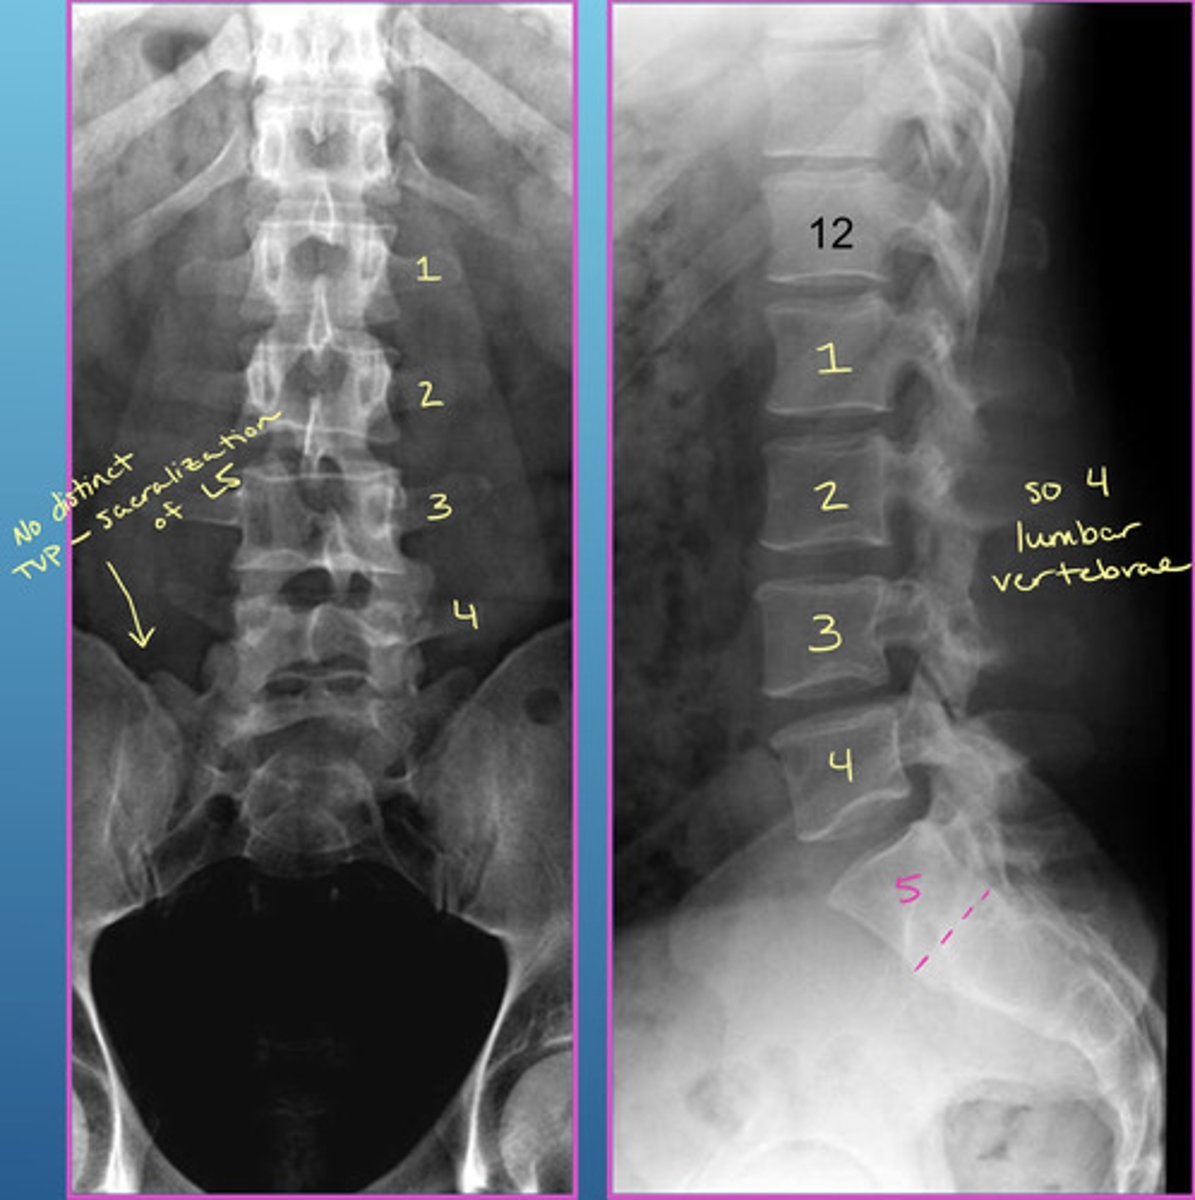

Image example of sacralization of L5